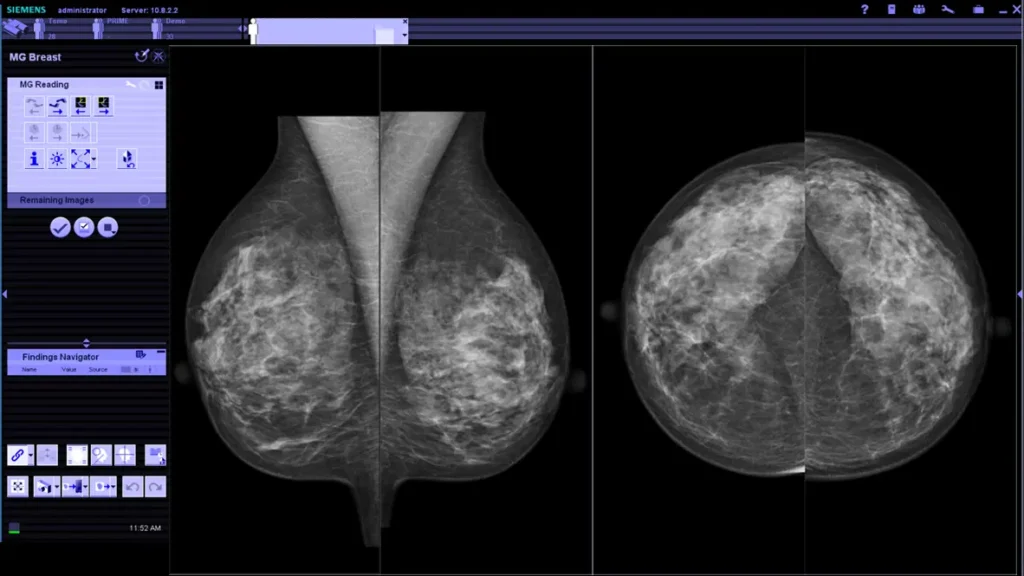

La Unidad de la Mujer de EXTOM está orientada a estudios de imagen enfocados en salud femenina, con énfasis en la detección temprana y caracterización precisa de hallazgos clínicamente relevantes. La resonancia magnética de mamas permite una evaluación multiparamétrica con alta sensibilidad, aportando información para diagnóstico, extensión de enfermedad y planificación terapéutica cuando existe sospecha oncológica. Complementamos el enfoque con estudios que apoyan prevención y seguimiento, priorizando protocolos estandarizados y reportes estructurados. La unidad trabaja con criterios de calidad, seguridad y correlación clínico-radiológica, para que cada examen se traduzca en información útil para decisiones médicas oportunas. Nuestra prioridad es brindar resultados confiables, con interpretación subespecializada y enfoque centrado en la paciente, manteniendo trazabilidad diagnóstica en el tiempo.

Imagen orientada a la salud femenina con énfasis en detección temprana y evaluación multiparamétrica. Protocolos estandarizados para diagnóstico, extensión y seguimiento clínico.